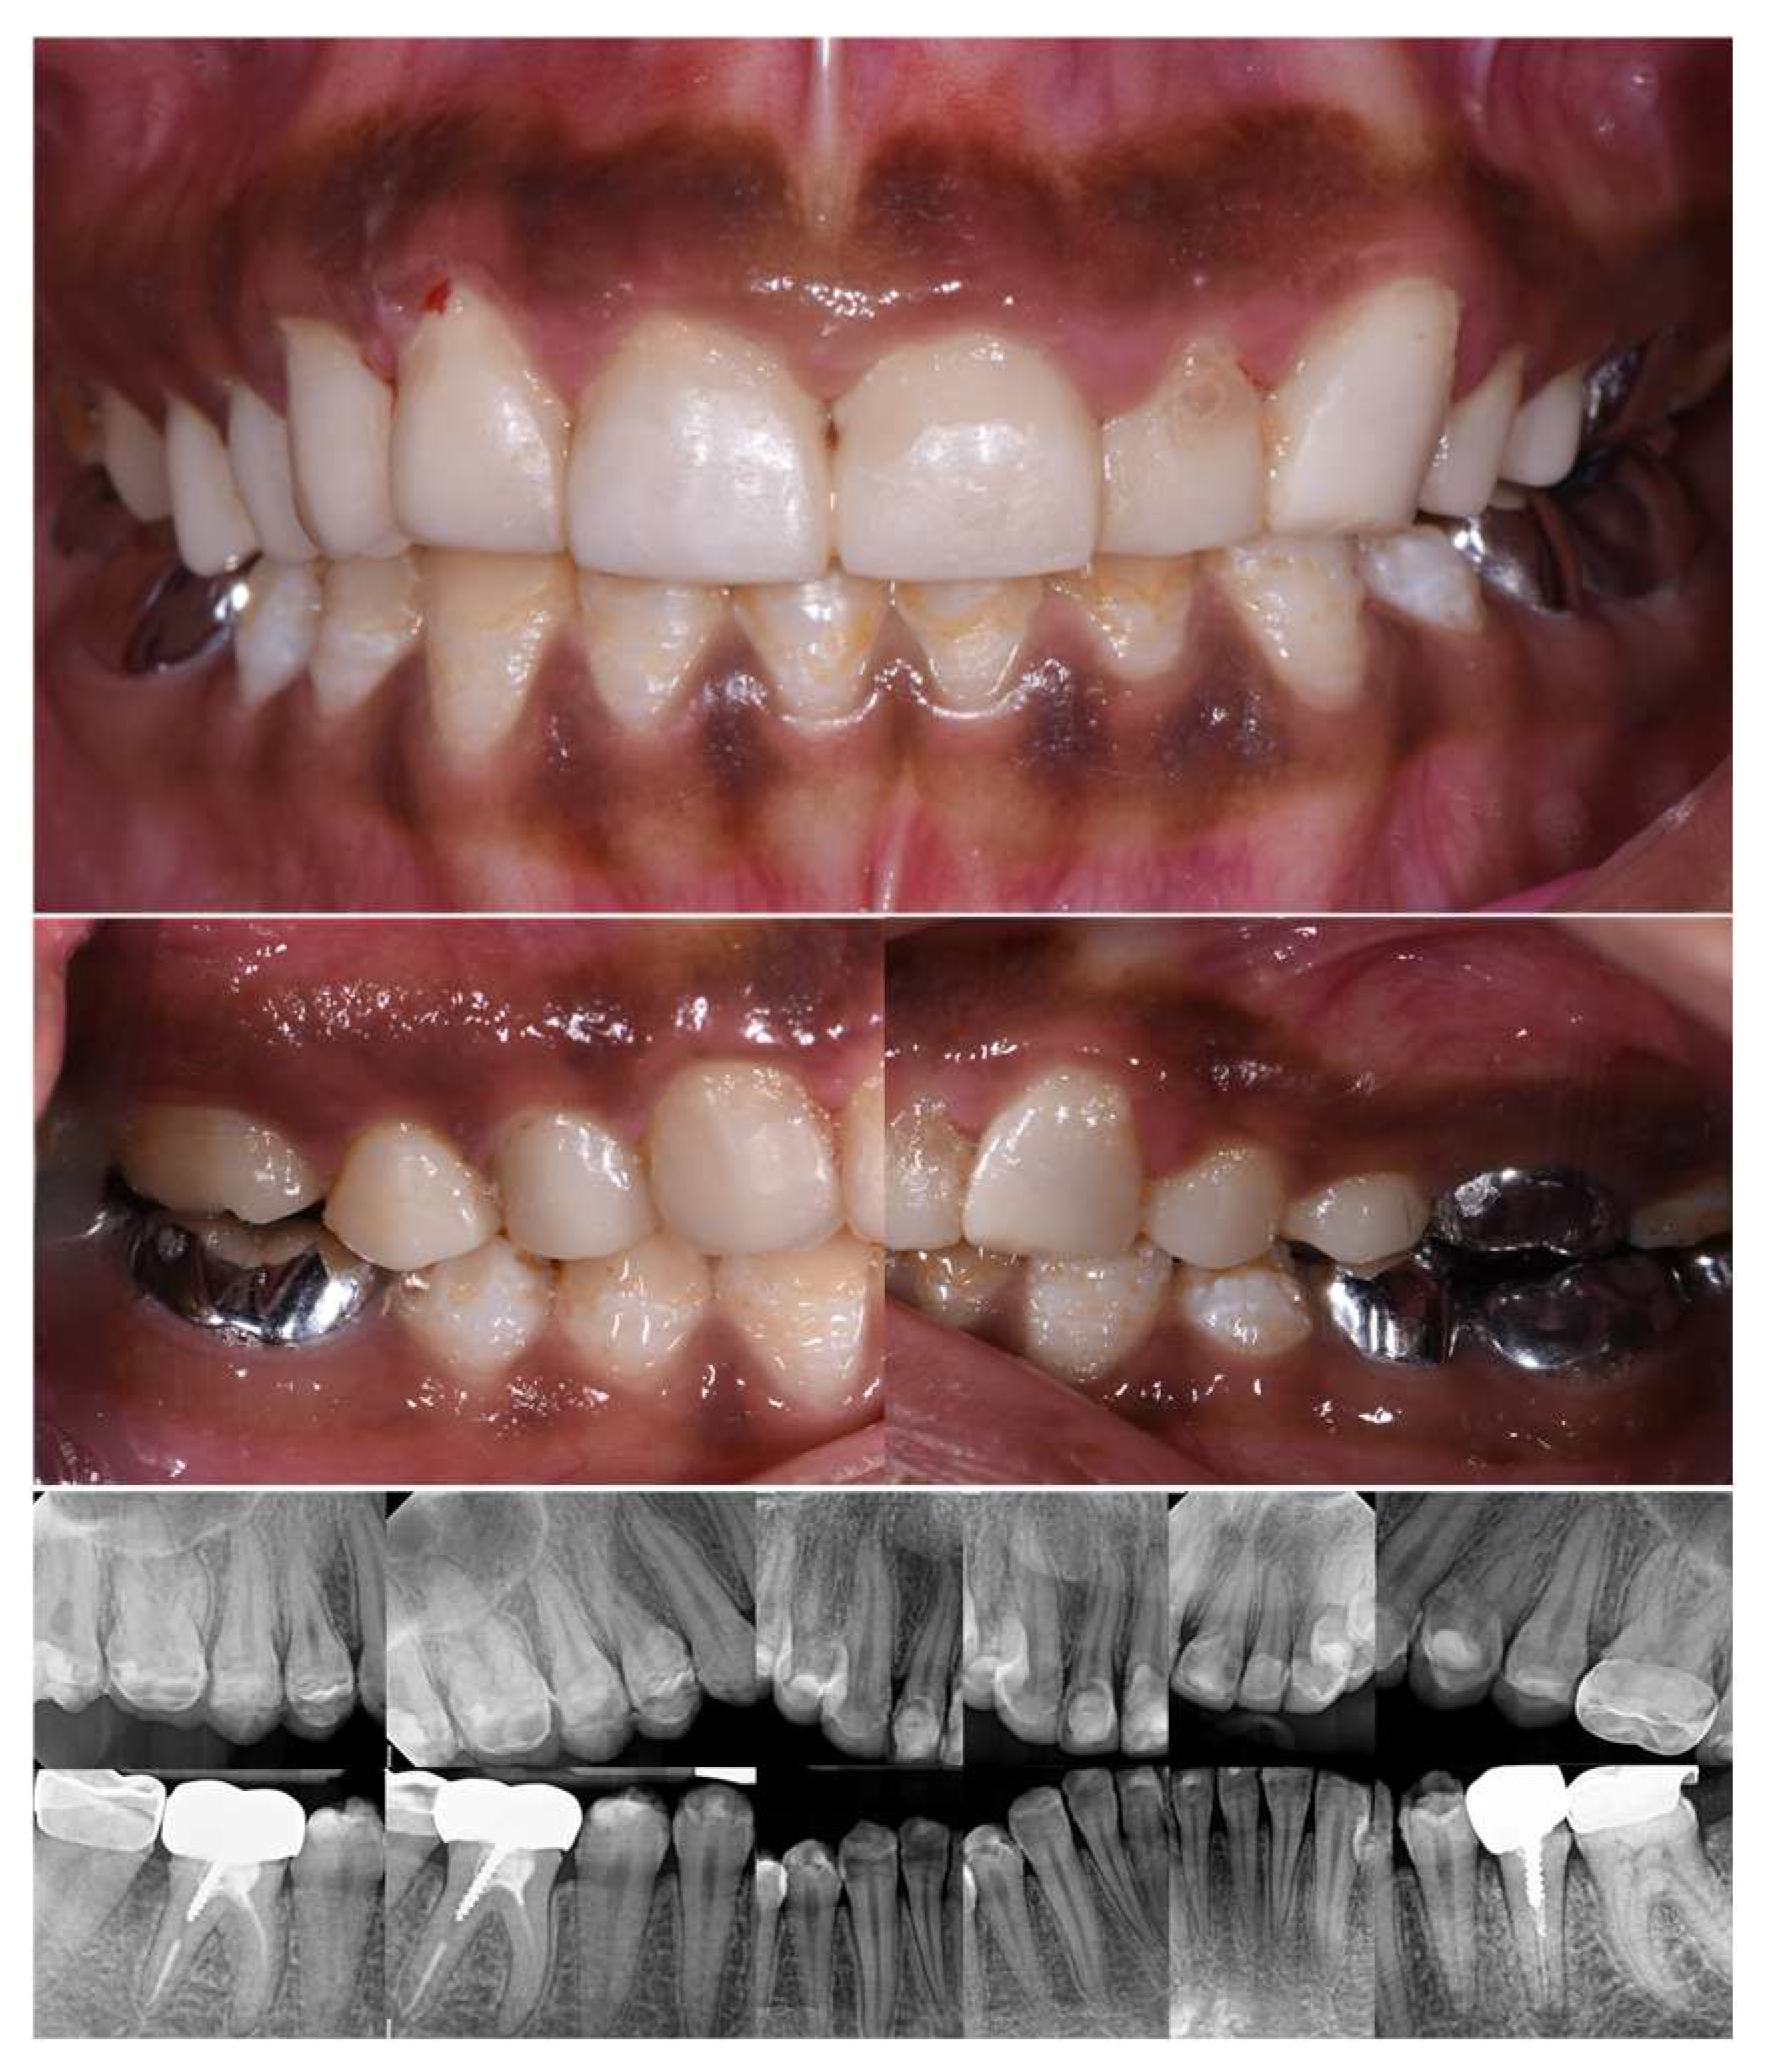

2.2. Clinical Examination

2.3. Radiographic Examinations